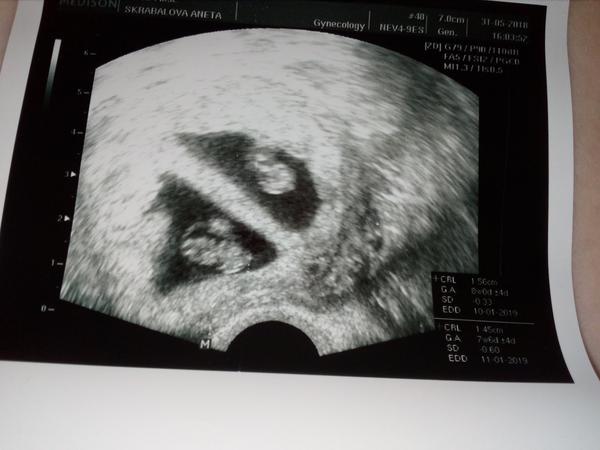

@kesinka2406 : jůů dvojičky, jsme nějak nepostřehlav diskuzi, tak to je dvojitá gratulace 🙂